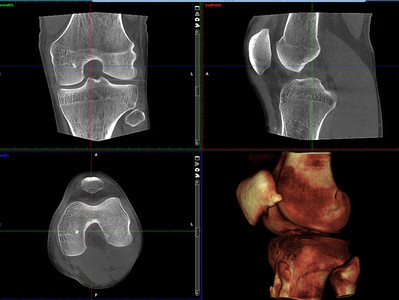

Mit den Aufnahmen des Digitale Volumentomograph der Firma SCS gewinnt der behandelnde Arzt Dank der ultrahochauflösenden Darstellung von Hartgewebestrukturen, nach nur wenigen Sekunden Aufnahmezeit, eine Diagnostiklösung auf dem neuesten Stand der Technik. Selbst feinste Brüche in den Extremitäten werden sichtbar. Durch die speziell entwickelte Positionierstütze wird sichergestellt, dass sich das zu untersuchende Körperteil immer genau im Sichtfeld befindet. Zudem ist für Extremitäten eine Aufnahme unter Belastung möglich, bei welcher der Patient während der Bildaufzeichnung in der Gantry steht. Eine Belastungsaufnahme des Fußgelenks oder Knies zeigt die Anatomie bei natürlicher Belastung.

Bildgebung des offenen CTs